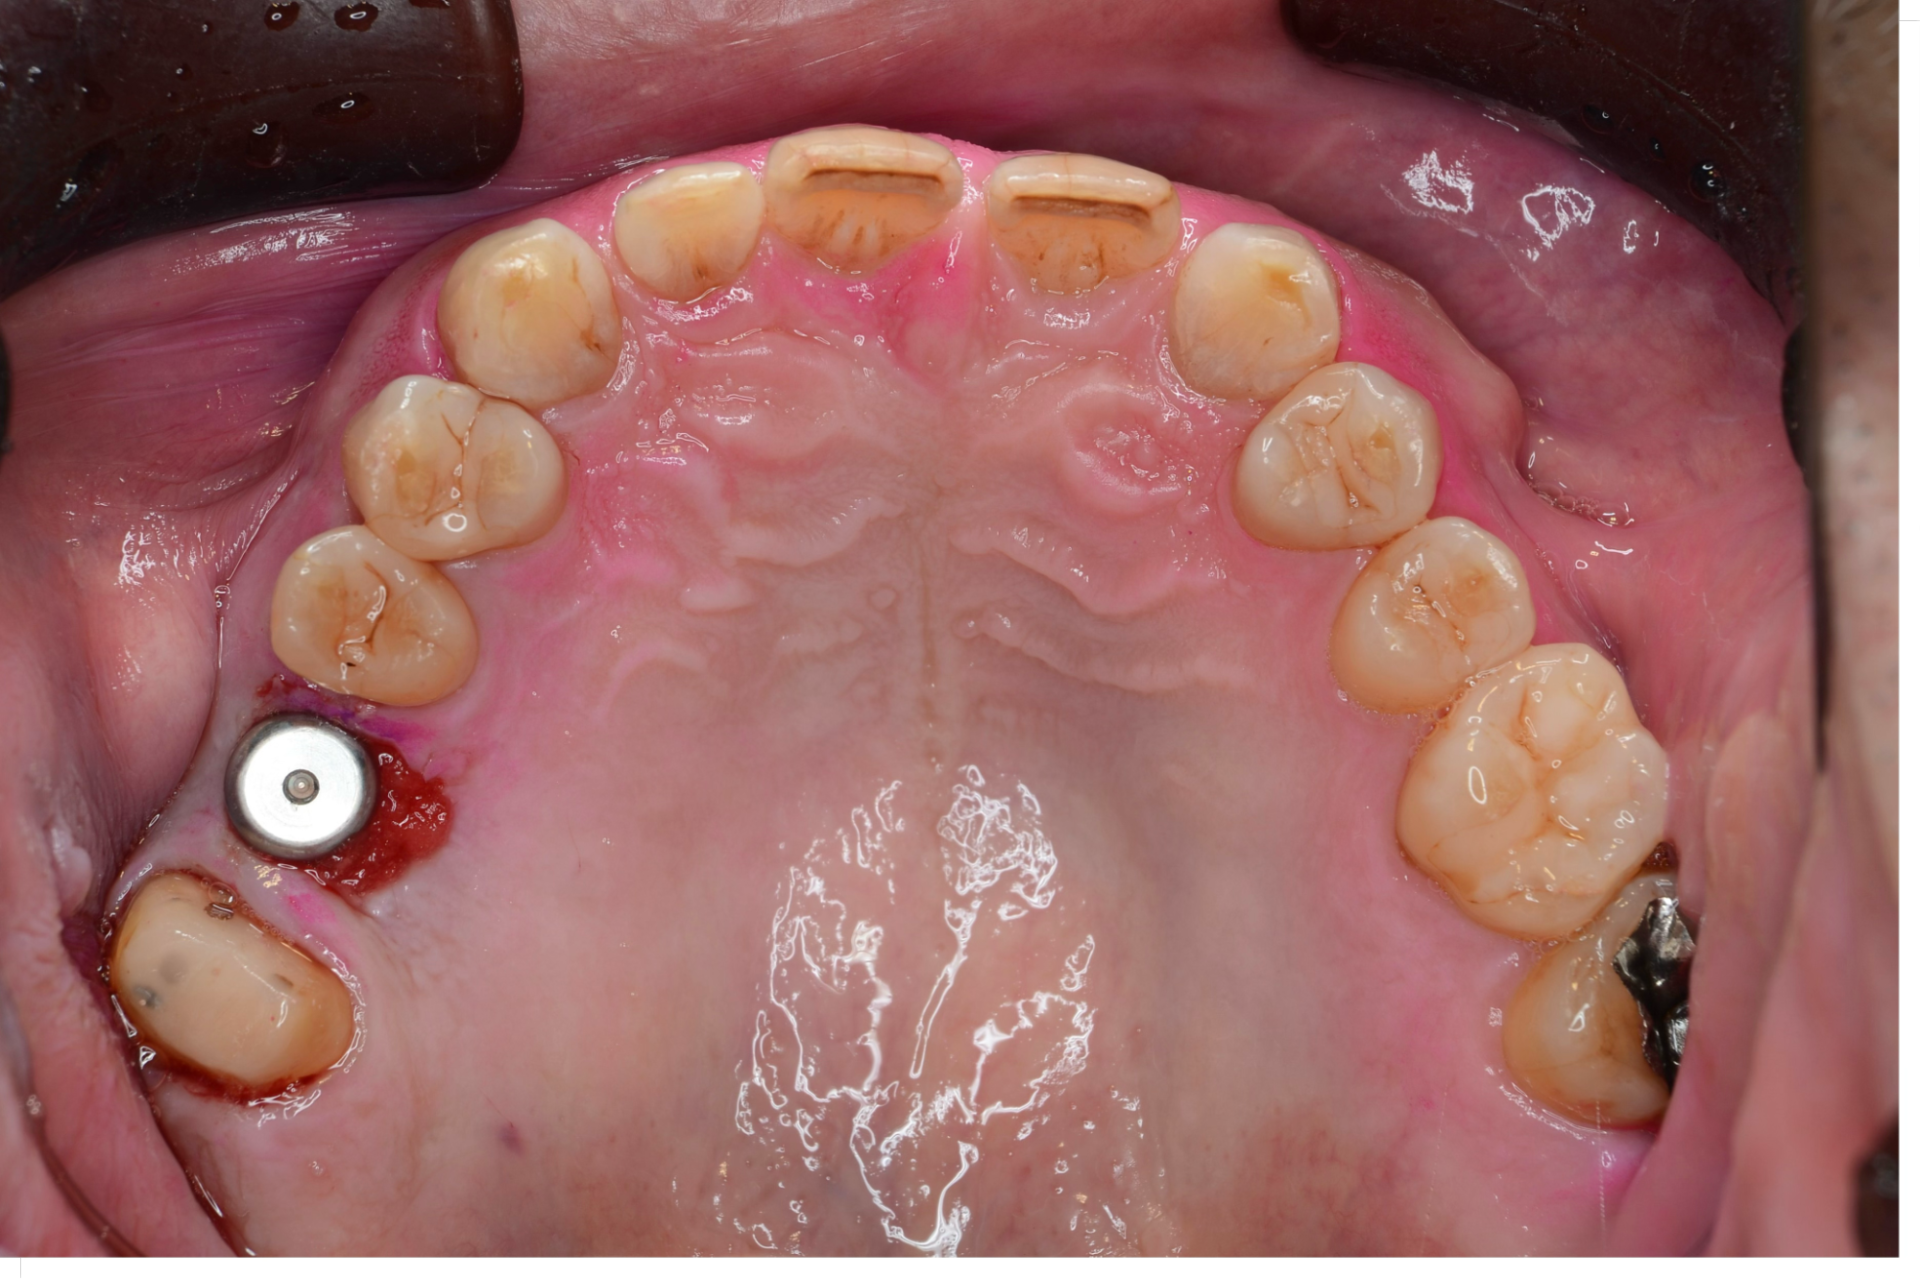

予定の位置に埋入されたインプラント